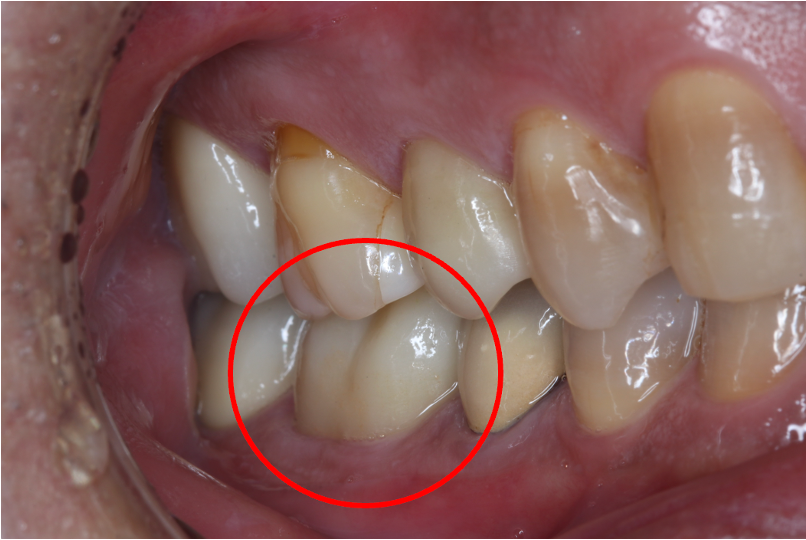

セラミック症例②

年齢 40代女性

治療期間 1ヶ月

治療内容 ジルコニア

治療箇所 右上6番

治療費用 100,000円